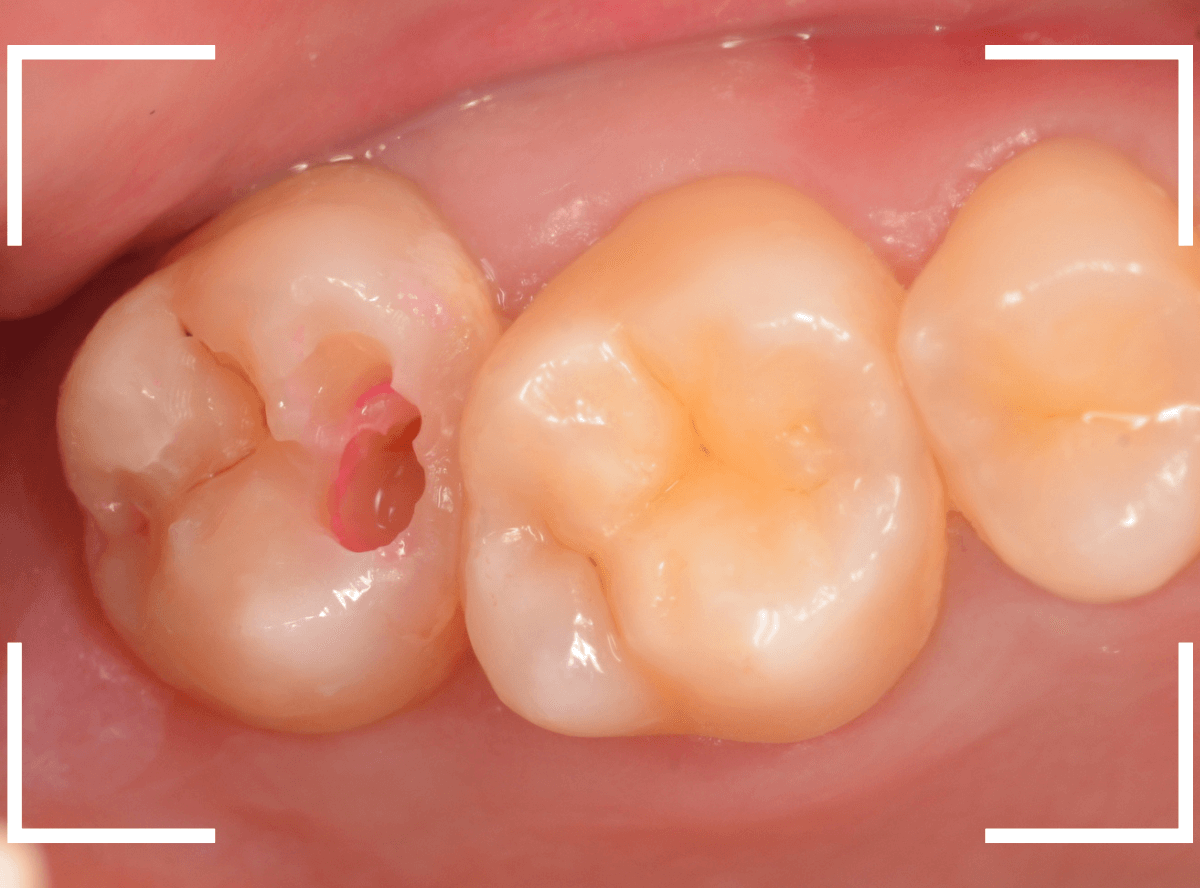

少し削ると、中からすぐに虫歯が出てきました。

ある程度、虫歯を除去したところで、う蝕検知液で確認します。

赤く染まっている部分が虫歯です。

まだまだ虫歯が中で残っている状況で、かなり深い虫歯なのが確認できます。